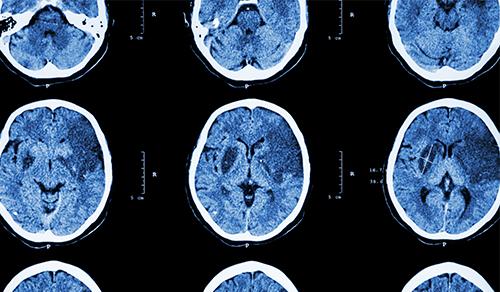

Innovative technologies and alternatives to traditional treatments are transforming the diagnosis and management of neurological conditions. In 2025, NewYork-Presbyterian physicians and surgeons from Columbia and Weill Cornell Medicine used sonication and convection-enhanced delivery to penetrate the blood-brain barrier, validated an adjunctive treatment for subdural hematoma, broadened access to spine surgery, advanced experimental therapies for neurodegenerative diseases, and more. Our specialists have been steadfast in reshaping the fields of neurology and neurosurgery in the pursuit of better patient outcomes and enhanced quality of care.

From cutting-edge research to compassionate patient practice, neurologists and neurosurgeons from Columbia and Weill Cornell Medicine are at the forefront of developing and applying the most advanced approaches to treat debilitating conditions affecting the brain and spine. With a broad range of focus on neurodegenerative and neurovascular disorders to malignant tumors, our innovative and advanced care is leading to new treatment options and enabling patients to achieve the best possible outcomes.